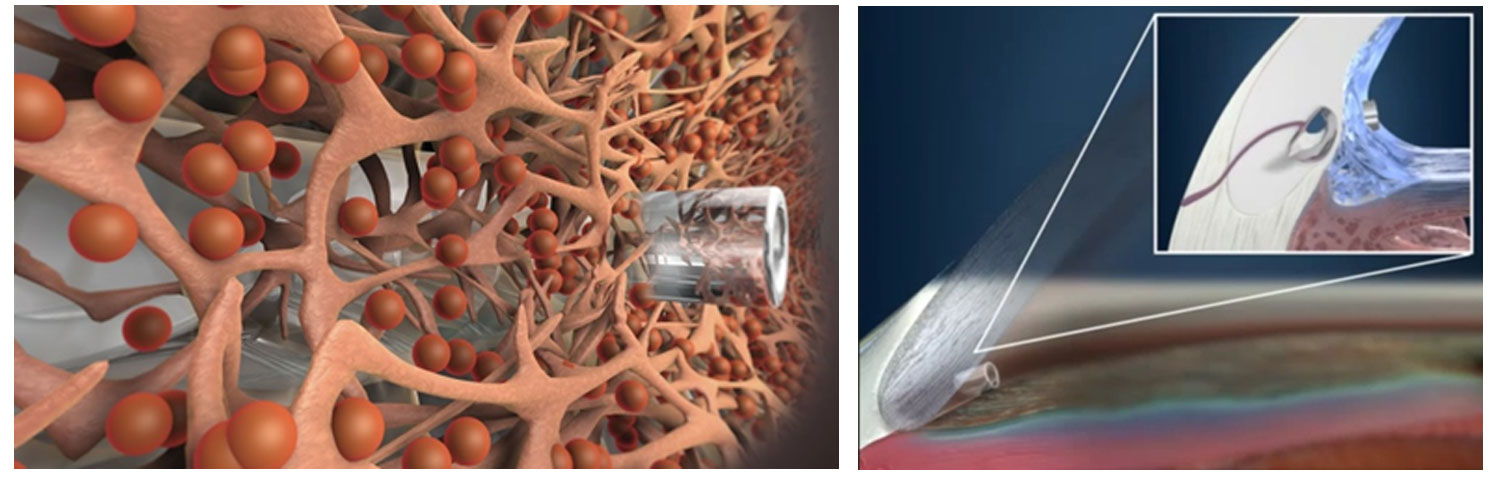

iStent®は開放隅角緑内障に対して眼圧を下降させる極低侵襲緑内障手術の際に使用されるMIGS(micro-invasive glaucoma surgery)デバイスです。単独での手術の際は自由診療となりますが、白内障手術と同時に行われる際には保険診療となります。

iStent®は、長さ横1mm縦0.12mmの非常に小さいデバイスです。緑内障手術は線維柱帯切除やEx-PRESS手術など各種の手術がありますが、今までの手術は目への侵襲が大きい手術でありました。

白内障手術の際に2.4mmの白内障手術創口からiStent®を線維柱帯にインプラントして、房水流出を妨げている線維柱帯に対して排出を改善し眼圧を下降させます。その為、侵襲の非常に少ない緑内障手術、極低侵襲緑内障手術として注目されております。臨床試験の結果では眼圧の下降と緑内障治療薬の低減が示されています。日本眼科学会HP[http://www.nichigan.or.jp/member/guideline/iStent.jsp]に詳細と論文がありますので、メリットデメリットなどご参考にして頂けますと幸いです。